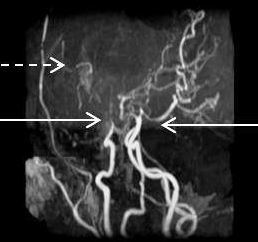

Moyamoya syndrome, characterized by progressive noninflammatory, nonatherosclerotic occlusion of bilateral intracranial arteries, is a classic complication that leads to stroke in children with Down syndrome.